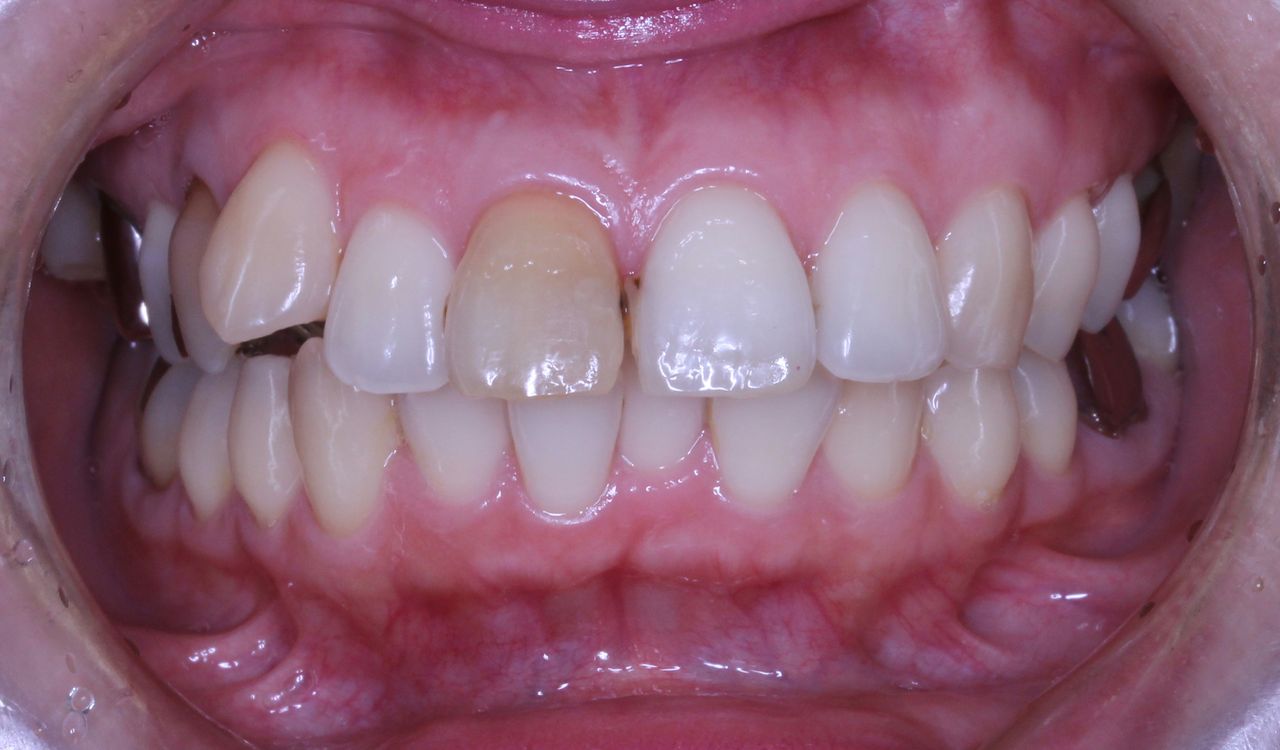

患者さんの主訴は口元をひっこめたいでした。

そうなると抜歯しての歯列矯正治療は必須です。また、口元の改善を考えると、前歯よりの歯を抜歯したほうが治療的には容易です。

上の歯列はどうでしょうか?

その患者さんの数年前の画像です

現在は他のクリニックで歯列矯正を一切しない方法で治療を開始しており、かみ合わせがおかしくうまくいっていないような気がするとのことでコメントを求めての来院でした。